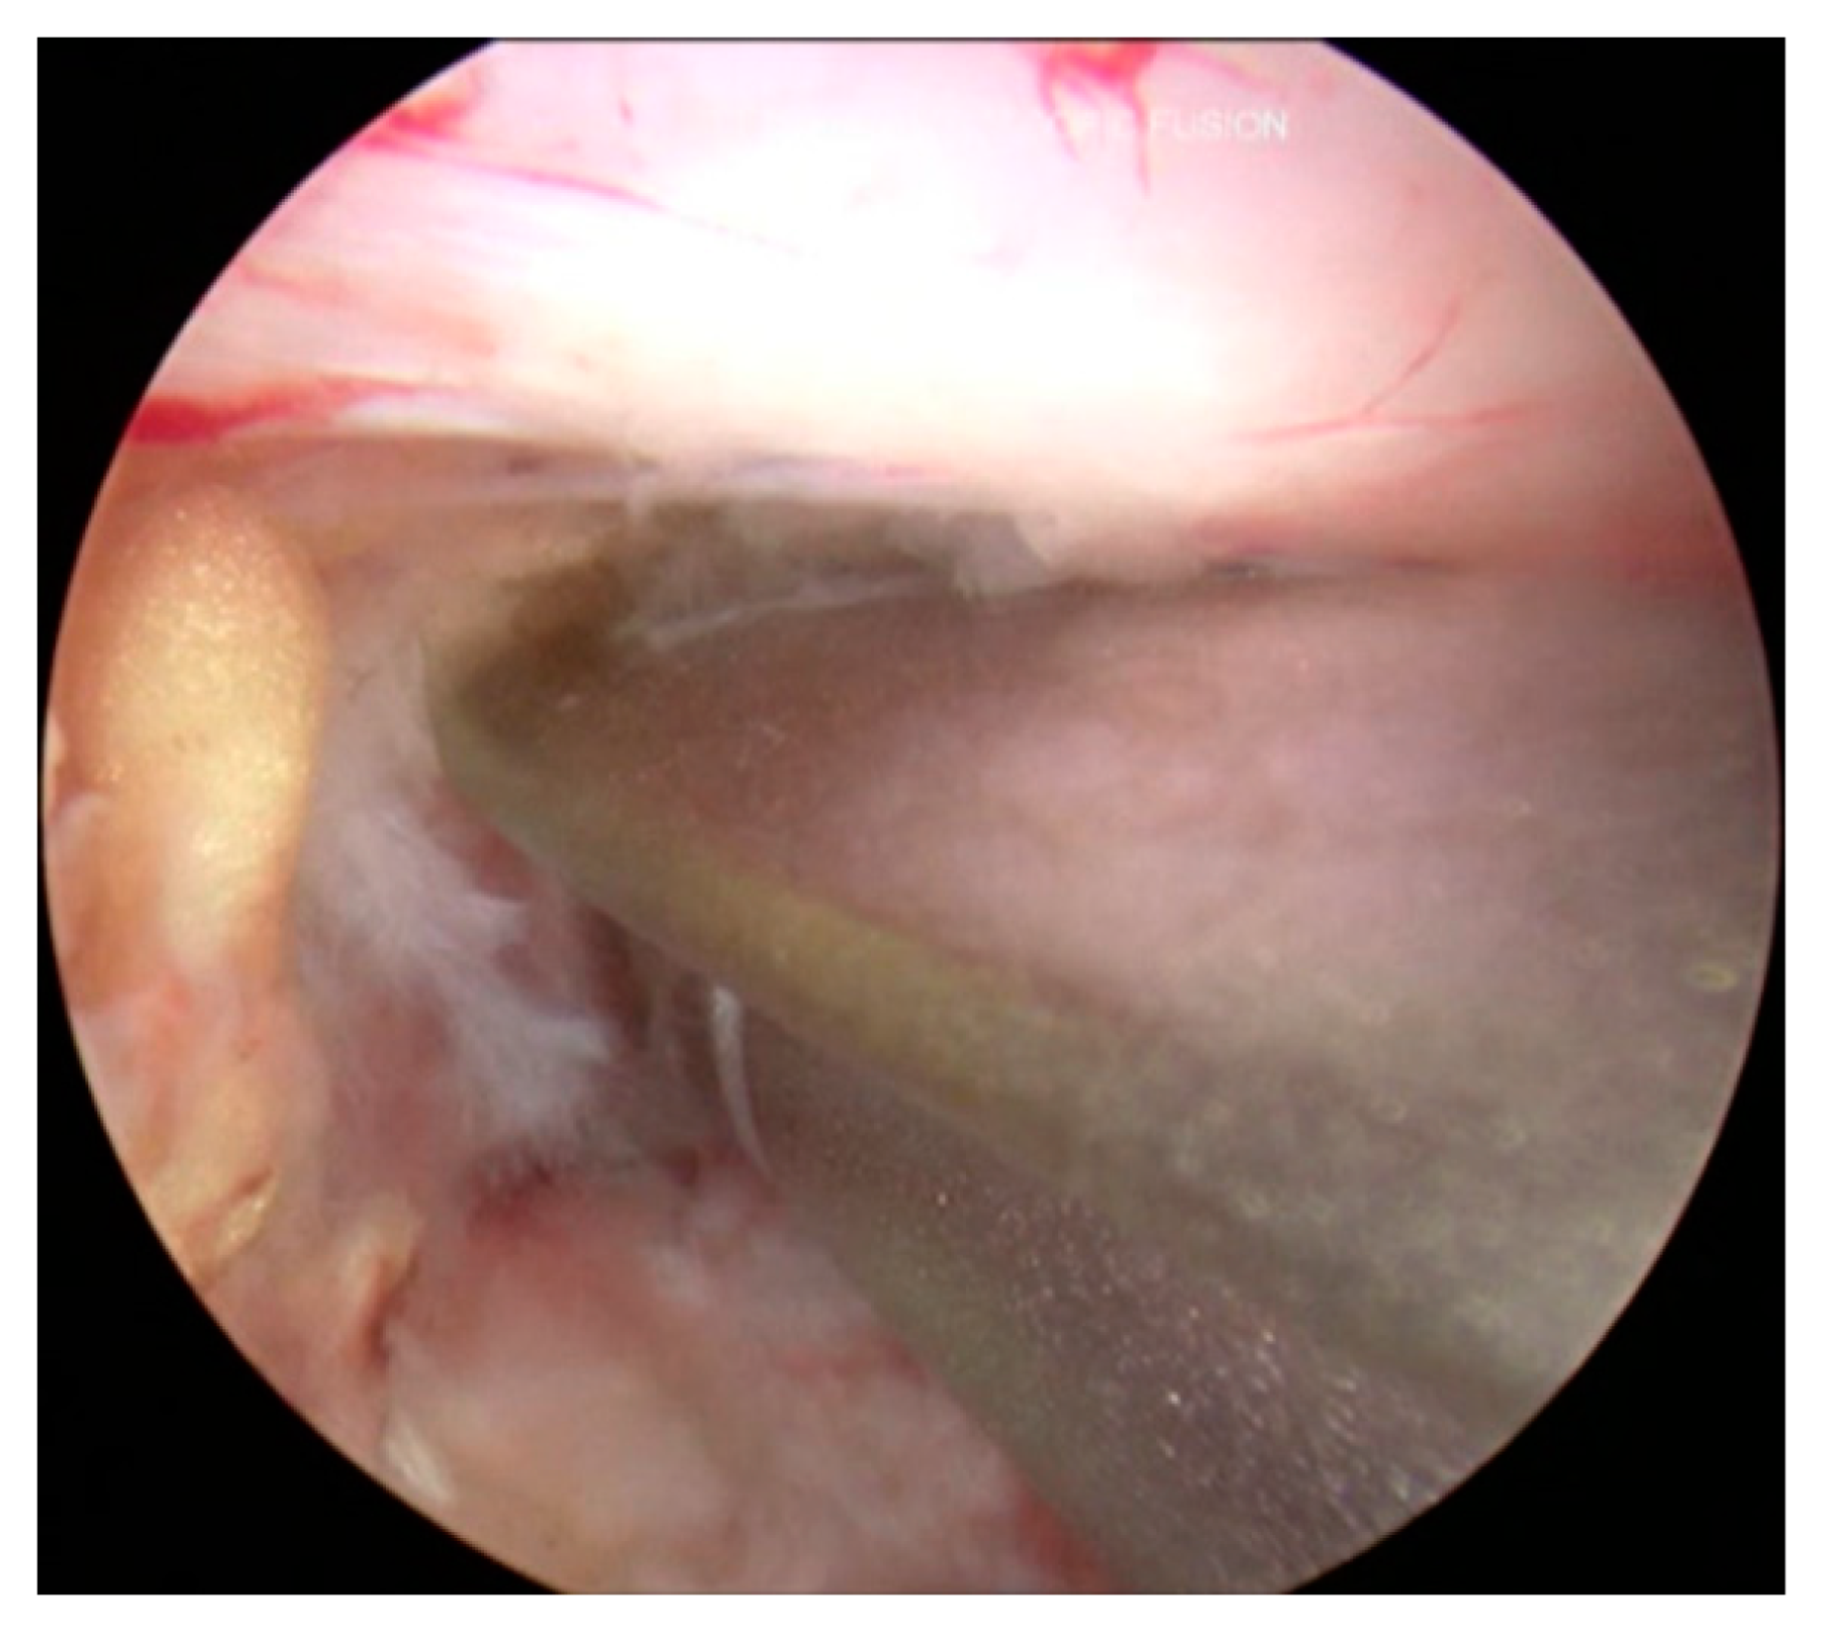

3.6. Decompression and Discectomy

3.7. Endplate Preparation